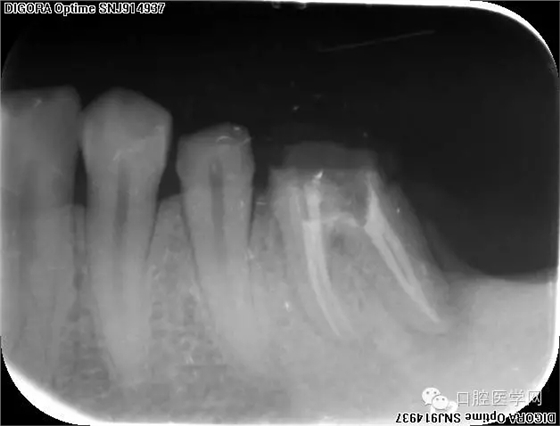

根充,拍片。

根管充填成功標(biāo)準(zhǔn)是X線片示根管充填嚴(yán)密,充填材料距根尖孔約1 mm 以內(nèi),允許少量根管糊劑超填。根管無側(cè)穿、無異物和器械分離。